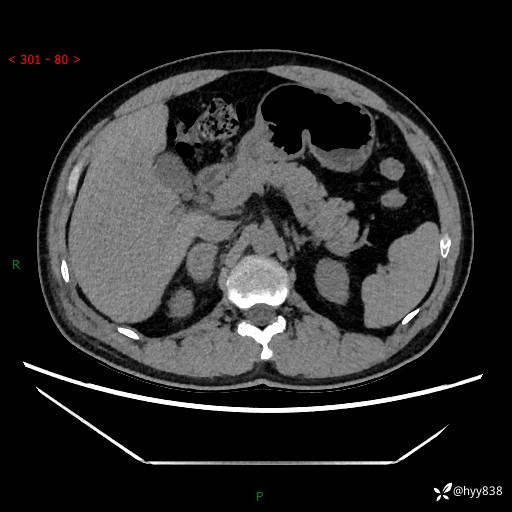

现病史:患者9月4日摔伤在深圳市宝安区中心医院行CT检查提示右侧肾上腺区结节(38*27mm),复查B超提示右侧肾上腺区可见一61*24mm异常低回声团,建议进一步检查。进一步完善增强CT后提示:右侧肾上腺区肿块及周围渗出改变,大致同前,考虑肾上腺腺瘤,不除外瘤内出血可能,否认阵发性头晕、头痛、出汗、乏力等不适,门诊以“ 右侧肾上腺肿瘤”收入住院。 起病来,患者精神、食欲、睡眠可,大便通畅,小便如上述,体力体重无明显改变。

肾上腺CT平扫

增强(动脉期+静脉期)

单侧肾上腺病变,鉴别诊断有哪些